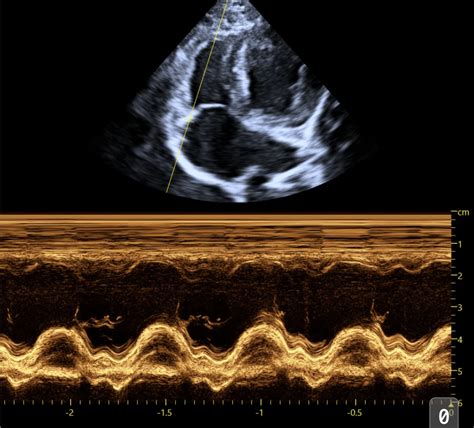

Alright, let’s start with the parasternal long-axis view , often called the PLAX. This is probably the most fundamental view you’ll learn. We get this by placing the ultrasound probe on the chest wall, typically to the left of the sternum, between the ribs. The name itself gives us clues: ‘parasternal’ means next to the sternum (breastbone), ‘long-axis’ means we’re looking at the heart lengthwise, from the base (where the great vessels exit) towards the apex (the pointy tip). In this view, you guys will see the left ventricle (LV) , the left atrium (LA) , the aortic outflow tract , and the mitral valve . We can assess the size of the LV, its wall thickness, and how it’s contracting. We can also get a good look at the mitral valve’s function and the aortic valve. This view is absolutely critical for assessing systolic function (how well the heart pumps blood out) and diastolic function (how well it relaxes and fills). We often use it to measure things like ejection fraction and fractional shortening, which are key indicators of the heart’s pumping efficiency. It’s like getting a side-profile picture of the heart’s main pumping chamber and its exit route. You can also visualize the interventricular septum and the posterior wall of the left ventricle, comparing their thickness and motion. It’s a fantastic starting point for identifying chamber enlargement, hypertrophy (thickening of the heart muscle), or dilation (enlargement). Don’t underestimate the power of this single view; it provides a wealth of information for initial cardiac assessments. We often begin our systematic scan with the PLAX, orienting ourselves before moving on to more specialized views. It sets the stage for understanding the overall cardiac architecture and function.

2. The Parasternal Short-Axis View (PSAX)

Next up, we have the parasternal short-axis view , or PSAX. This is like taking a slice through the heart, perpendicular to the long axis. We obtain this view by rotating the probe 90 degrees from the PLAX, still keeping it on the chest wall. The beauty of the PSAX is that it allows us to see the heart’s chambers in cross-section. We can get short-axis views at different levels : the aortic valve level, the mitral valve level, and the papillary muscle level (which is deeper in the ventricle). At the mitral valve level , we see the LV, the LA, and the two leaflets of the mitral valve appearing like a fish mouth. This is super useful for assessing mitral valve morphology and function, especially for conditions like mitral valve dysplasia or degeneration, common in older dogs. At the papillary muscle level , we see the LV cavity and the two papillary muscles within it. This view helps us evaluate the global contractility of the LV free wall and septum. And at the aortic valve level , we see the aorta , the right ventricle (RV) , and the three cusps of the aortic valve. This is great for looking for things like aortic valve stenosis or vegetation (like those nasty endocarditis growths). The PSAX is invaluable for assessing the relative sizes of the ventricles, the thickness of the ventricular walls, and the overall shape of the LV cavity. It helps us confirm findings from the PLAX and identify subtle abnormalities. It gives us a bird’s-eye view of the internal structures, allowing for a comprehensive assessment of the ventricular walls and their synchronized contraction. You can truly appreciate the circularity of the left ventricle here, which is a sign of healthy function, or an elliptical shape which might indicate issues. It’s a fantastic way to get a comprehensive understanding of the heart’s chambers and their immediate surrounding structures.